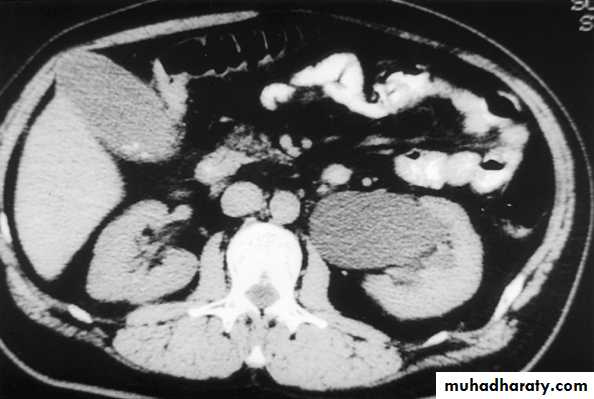

Ct enhanced

Big simple renal cyst(non enhancing mass homogenous) treatment is conservative or drainge if symptomaticWhat's the Diagnosis?